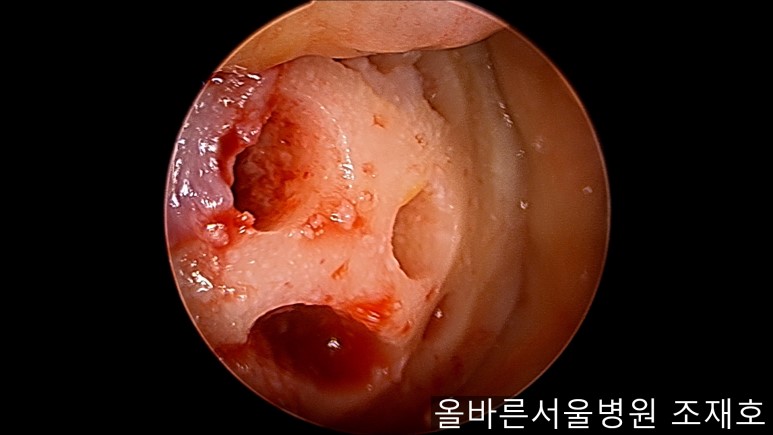

通过关节镜图像可看到:由于内侧股骨髁软骨损伤骨头已经显露出来。

image_9824311181519375935940.jpg

胫骨上端的软骨损伤严重,也露出了骨头。

image_9926851221519375935929.jpg

正是缺失软骨的部位碰到一起,引发剧烈疼痛,腿部逐渐变形。